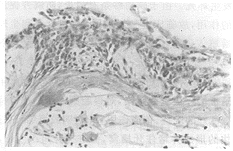

摘要 目的: 建立免疫功能正常小鼠肾囊膜下移植舌癌模型。材料和方法 :利用SRCA技术,建立移植舌癌模型,观察移植前后瘤体大小的变化,并对移植瘤进行病理切片观察。结果: 舌癌移植后第6天瘤体增长率为87.8%(7/8)(P<0.05),病理切片证实其为高分化性鳞癌。结论: 小鼠肾囊膜下移植舌癌模型的建立具有可行性,它可为舌癌的基础与临床研究提供一个经济、快速、高效的动物模型。

Abstract Objective: To set up a model of tongue cancer that a human tongue xenograft was transplanted under the renal capsule of normal immunocompetent mouse. Materials and Methods: SRCA was used to set up a transplanted model of tongue cancer, and the variation of tumor size was measured between day of sacrifice of the mouse and day of implantation, and the histologic morphology of transplanted tumor was observed. Results: On the 6th day after tongue xenografts were implanted, the growth rate of xenografts was 87.8%(7/8) (t test, P<0.05), and pathology sections proved that the transplanted tumor were highly-differentiate squamous cell carcinoma. Conclusions: It is feasible to set up the mouse subrenal capsule model of tongue cancer, which can provide an inexpensive, rapid, and efficient model for the study of tongue cancer.